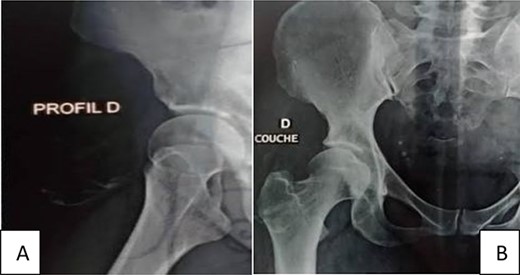

Radiographic examination by panoramic radiography showed thickening of the soft tissue of the right hip with calcifications (Fig. 1). Magnetic resonance imaging (MRI) revealed a well-circumscribed mass of the upper part of the anterior compartment of the thigh, non-attached to bone structures, measuring 11 × 4 cm. It has a high signal intensity on Tl and low signal intensity on T2, without enhancement after injection of gadolinium (Fig. 2) A diagnosis of lipoma was rendered.

Standard X-ray of the hip profile (A) and face (B) with thickening of the soft tissue of the right hip with dispersed calcifications.